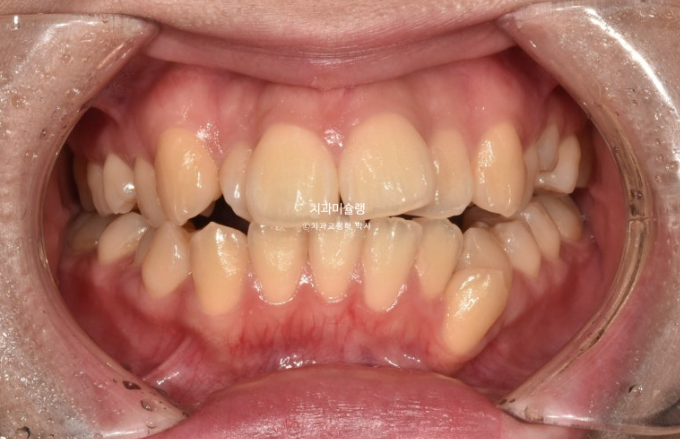

23년 10월 교정치료를 이해 온 30대 환자분입니다.

약 2mm 정도의 중심선 불일치 그리고 덧니가 보입니다.

개방교합도 있고

30년간 공간이 없어서 미처 내려오지 못한 작은어금니도 있습니다.

덧니가 워낙 심해 작은어금니 4개 발치가 불가피한 상황입니다.